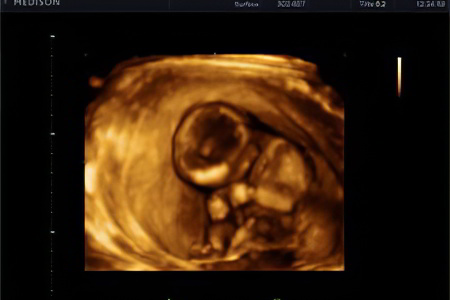

Что показывает УЗИ?

Если ваш акушер-гинеколог еще не назначил первое плановое ультразвуковое исследование для оценки состояния плода, сделайте это. Оптимальный период для УЗИ — с 10 по 14 неделю беременности.

Во время исследования можно получить следующие данные:

- Срок беременности;

- Предполагаемая дата родов;

- Состояние матки и плаценты;

- Количество плодов;

- Размер плода, его активность и особенности развития;

- Наличие факторов, указывающих на хромосомные аномалии.

На данном этапе можно выявить возможные пороки развития плода, поэтому ультразвуковое исследование является частью скрининга, который проводится в каждом триместре беременности.

Скрининг на 13 неделе

Первый этап скрининга развития ребенка направлен на выявление генетических и хромосомных аномалий. Он включает ультразвуковое исследование и биохимический анализ крови, которые помогают обнаружить признаки синдрома Дауна и синдрома Эдвардса. Во время УЗИ специалисты оценивают толщину и прозрачность воротниковой зоны, проверяют наличие и размеры носовой кости, а также выявляют видимые дефекты развития.

Если результаты скрининга показывают повышенный риск аномалий или хромосомных нарушений, женщине рекомендуется обратиться к генетику для консультации и пройти дополнительное обследование. Важно помнить, что высокий риск не всегда подтверждается наличием патологии, и результаты скрининга не следует воспринимать как окончательный диагноз.